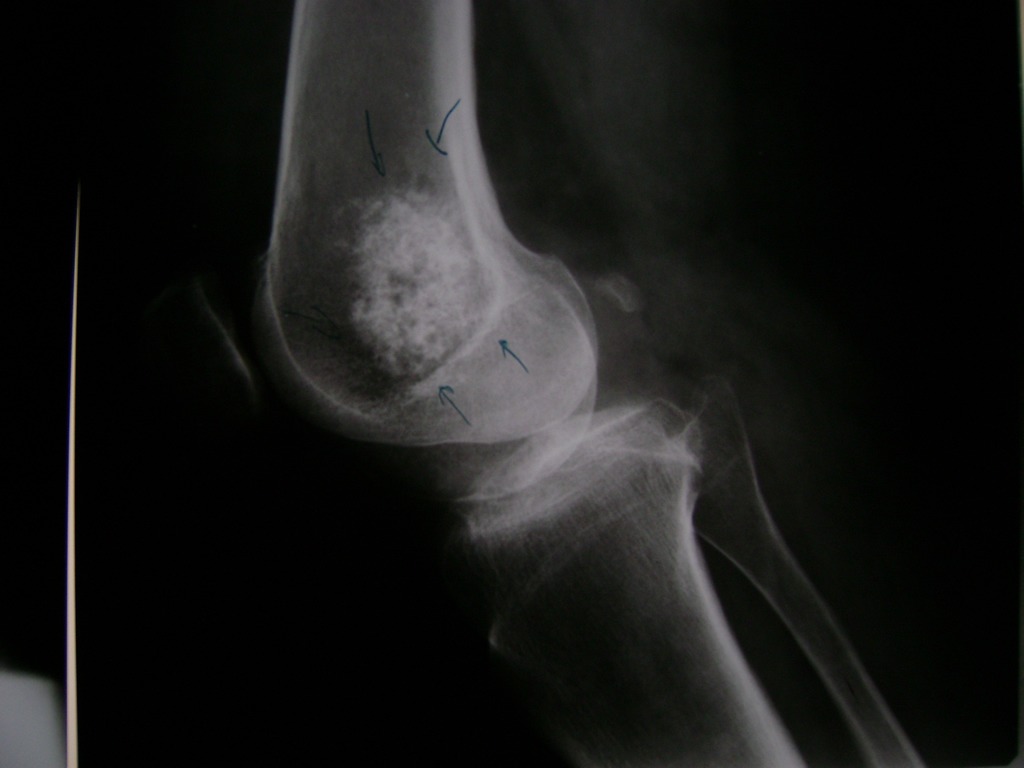

La artroscopia de rodilla es un cirugía en el cual la estructura interna de la articulación es examinada ya sea para realizar un diagnostico o para realizar un tratamiento, este procedimiento se realiza utilizando un instrumento parecido a un pequeño tubo llamado artroscopio.

La artroscopia se popularizo en 1960 y hoy en día es muy común en todo el mundo. Típicamente, es realizada por cirujanos ortopédicos de manera ambulatoria. Cuando se realiza de manera ambulatoria los pacientes pueden regresar a casa después de la operación, no se requiere quedarse en hospital.